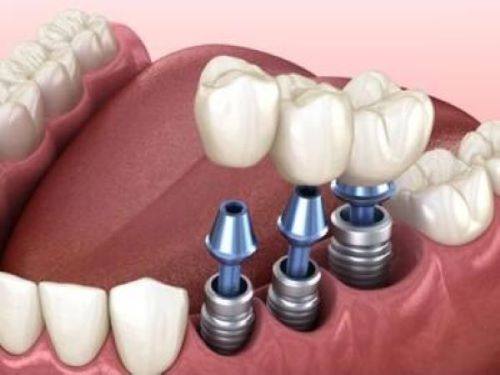

活动义齿一般多少钱一颗费用?2026年最新价格揭秘! 文章揭秘2026年活动义齿最新价格。通常镶活动假牙一颗1000 - 3000元,不同类型费用有别。如隐形义齿1000 - 1200元,便宜但寿命短、咀嚼差;钴铬合金等1500 - 2000元,强度好、使用久;纯钛基托2000 - 3000元,舒适美观。此外,地区、医院等级和医生水平也影响价格,选义齿要综合考量。 活动义齿 2026年03月04日 0 点赞 0 评论 7 浏览

活动义齿哪种最舒服还不伤害基牙?揭秘3种最佳选择! 本文围绕“活动义齿哪种最舒服还不伤害基牙”展开。首先强调了活动义齿舒适与护基牙的重要性,接着介绍了纯钛金属基托活动义齿等三种义齿的特点,包括舒适度、对基牙的影响、价格等。还给出选择建议,要考虑口腔状况、经济因素,并听取医生建议。最后提醒佩戴后注意适应期、清洁和饮食,综合考量选适合自己的义齿。 活动义齿 2026年03月04日 0 点赞 0 评论 12 浏览

补一颗活动义齿多少钱?揭秘真实费用与选择技巧! 本文围绕补一颗活动义齿的费用及选择技巧展开。费用大致在100 - 300元,受材料、修复难易、医院级别、当地经济等因素影响。不同材料义齿各有特点和价格区间。选择时要综合自身情况,选正规机构,多对比。此外,后期维护有成本,需正确佩戴清洁。提醒大家综合考量价格、质量和舒适度,必要时咨询医生。 活动义齿 2026年03月04日 0 点赞 0 评论 7 浏览